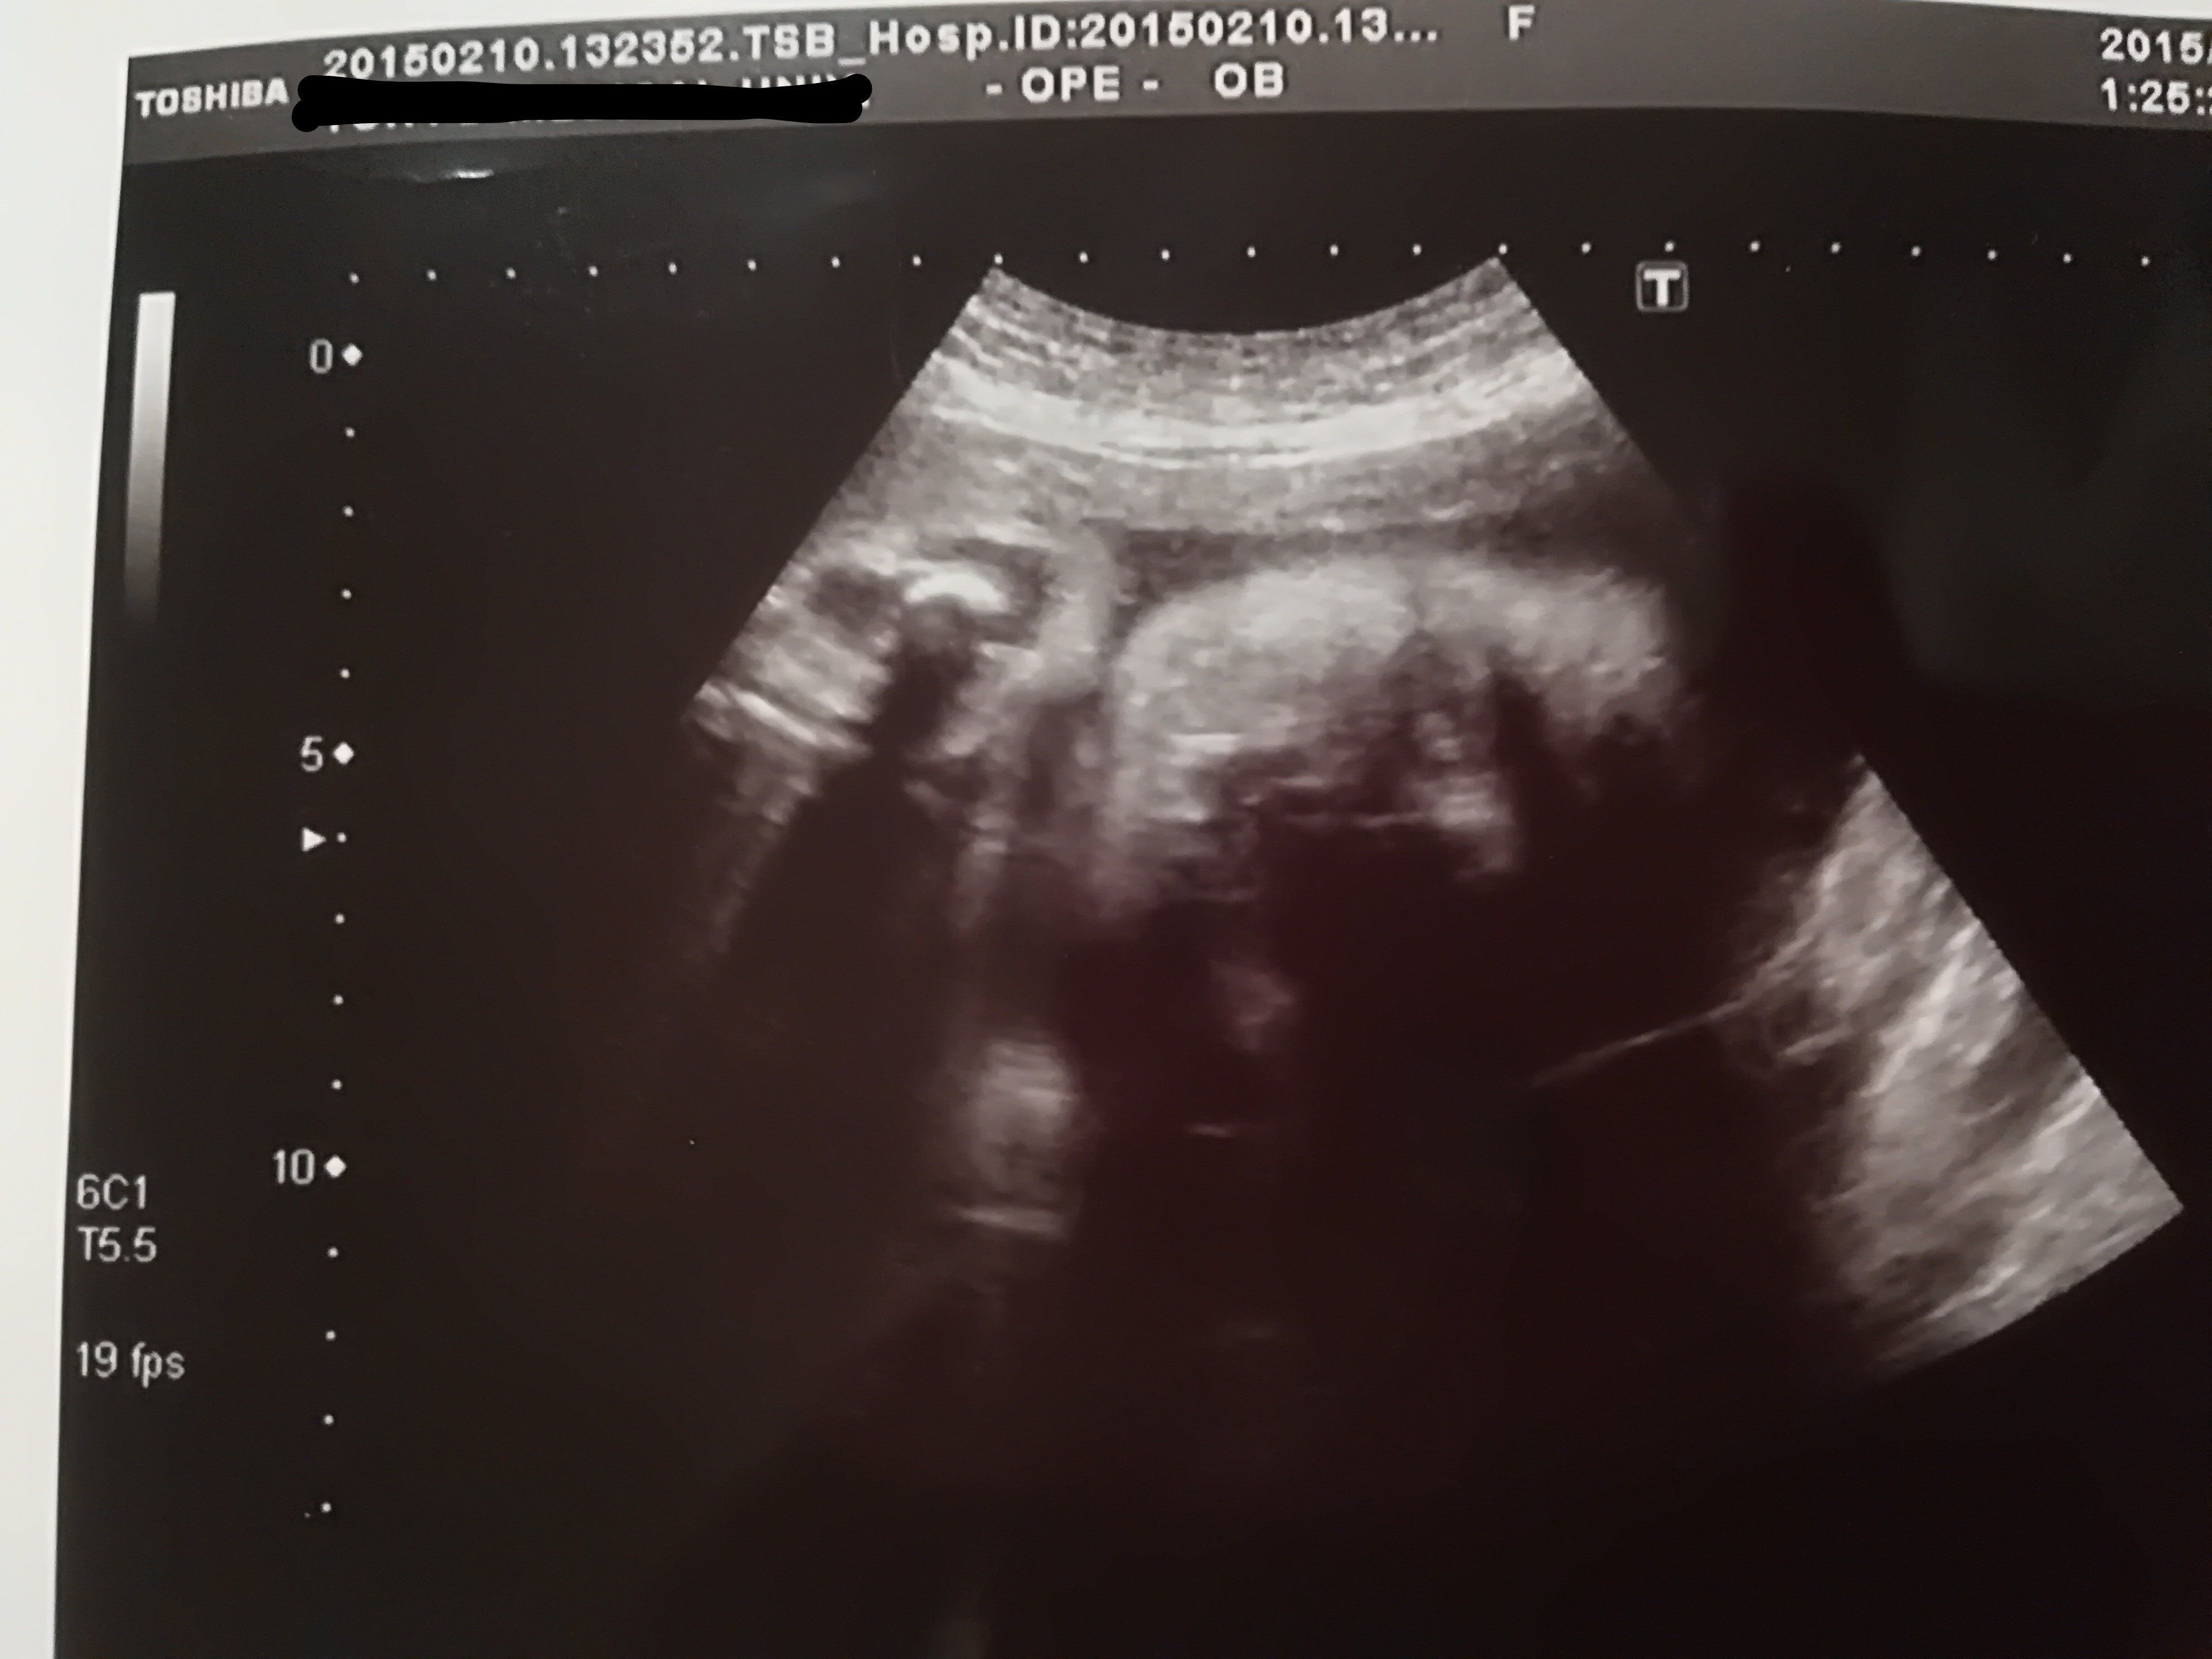

妊娠11週目のエコー写真

頭がはっきり確認できました。そろそろ、つわりがマシになるはずなのに、今度は喉が塞がる感覚で物が飲み込みにくくなるという症状が現れました。耳鼻科では、心身症を疑われて落ち込みました。点滴のおかげか、尿にケトン体が出るまでには至りませんでした。毎日、ネットで他の人のつわりが何週目で終わったのかを調べて励みにしましたが、実際うつ状態だったと思います。